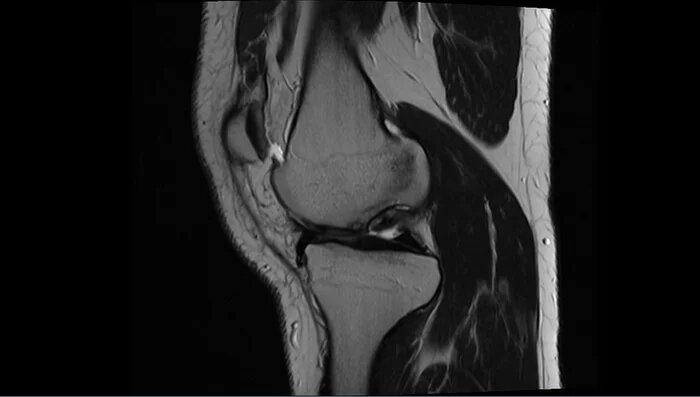

МРТ, КТ призывника с жалобами на боли в правом коленном суставе, "заклинивание" в суставе.

По задне-внутренней поверхности медиального мыщелка правой бедренной кости определяются участки субхондральных изменений-костные структуры размерами 11х5мм, 8х3мм,гиалиновый хрящ под ними не прослеживается. Заключение :Рассекающий остеохондрит (б.Кенига)правого коленного сустава.